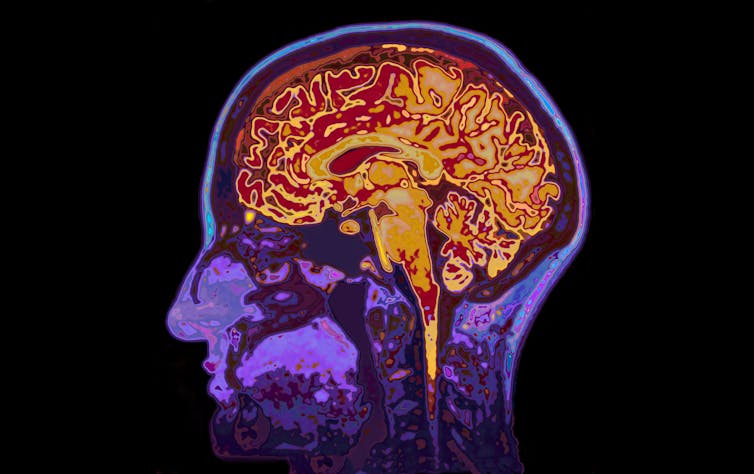

The lonely brain

When we spend quality time with another person, we experience intrinsic joy. Brain scanning studies show that subcortical brain regions, such as the ventral striatum, which plays an important role in motivation, are activated when receiving monetary and social rewards.

When we feel lonely and rejected, brain regions associated with distress and rumination are activated instead. This may be due to evolution driving us to establish and maintain social connections to ensure survival. Lonely people also have a more negative focus and anxiously scrutinise people’s intentions. Sometimes this can become so strong that it makes us feel even more lonely – creating a vicious cycle.